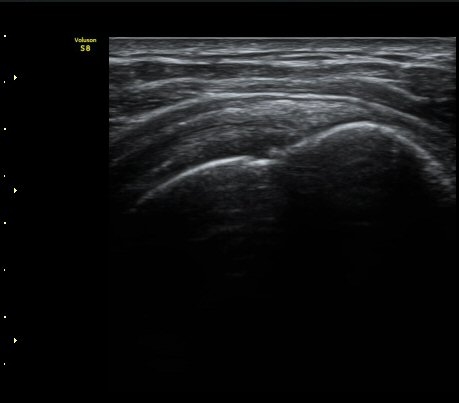

ÀÌµÎ¹Ú±Ù°Ç È¾´Ü¸é°Ë»ç¿¡¼­ ƯÀÌ ¼Ò°ßÀ» º¸ÀÌÁö ¾ÊÀ½(»çÁø 1, 2).